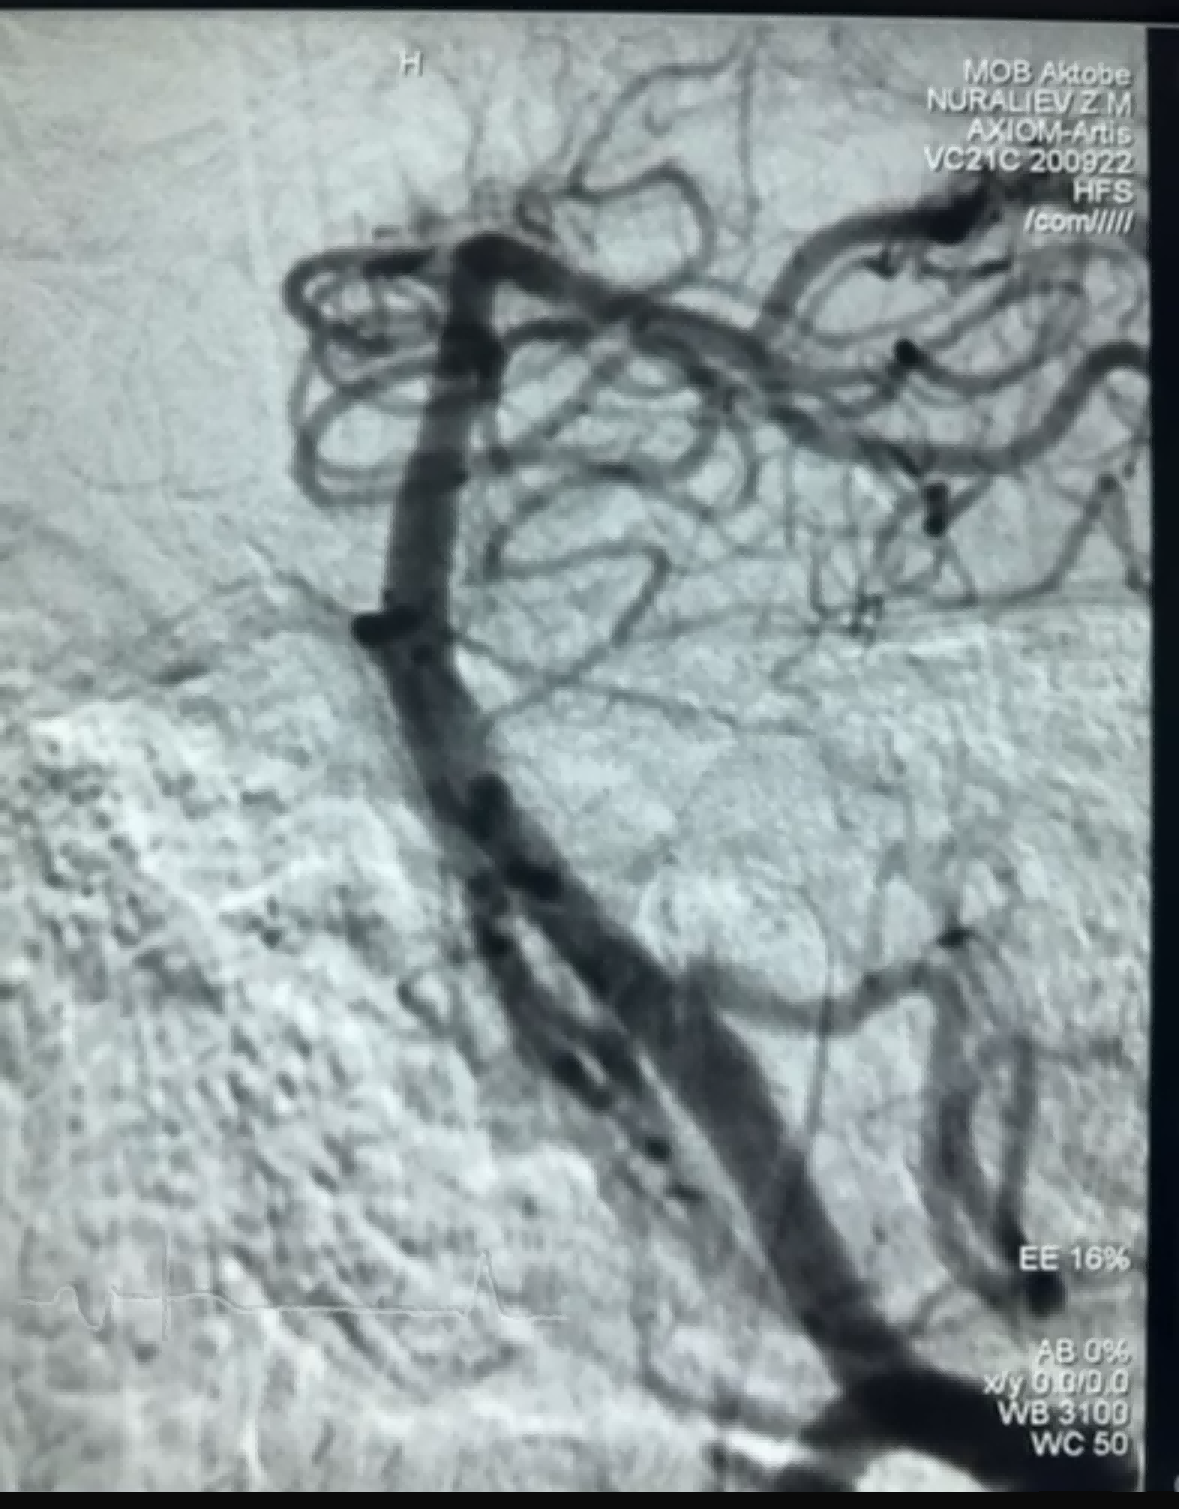

최근 NeuroSafe Medical Co., Ltd.의 Dredger Stent Retriever를 사용하여 성공적인 혈전 제거 사례가 있었습니다. Dredger Stent Retriever는 비침습적 소프트 팁을 가지고 있어 내막 손상 위험을 크게 줄이고, 주로 틈새 변화를 클램핑하여 혈전을 포획하는 고유한 특수 모양의 구멍 디자인을 가지고 있습니다.